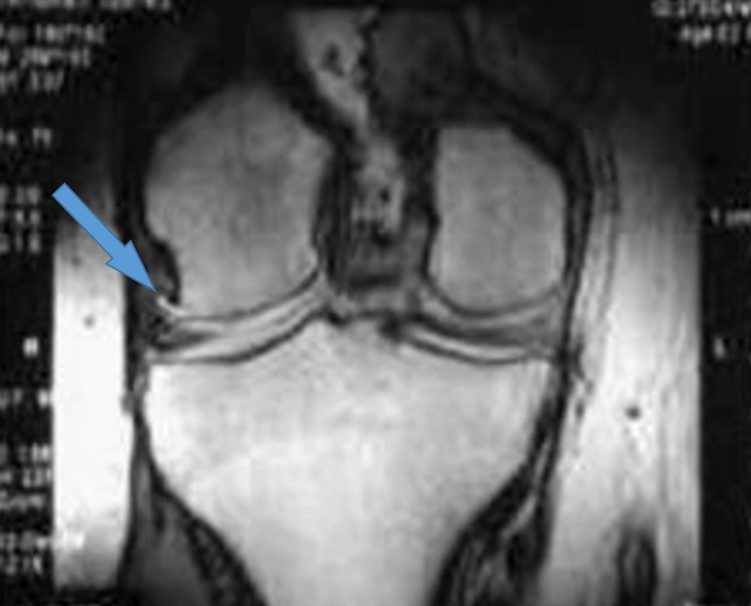

МРТ визуализация ОА коленного сустава (при первой Ro стадии)

Напомним, что на сегодняшний день в мире не существует рекомендаций по определению стадии ОА при помощи МРТ. Но, на начальных стадиях, МРТ дает более подробную картину состояния внутрисуставных структур. Именно визуализация при помощи МРТ помогает определить ОА на ранних стадиях и начать своевременное лечение.

И так, что мы увидим на МРТ при первой рентгенологической стадии ОА коленного сустава:

- 1. Отёк и неравномерное истончение суставного хряща.

- 2. Дегенеративные изменения (повышение интенсивности МР сигнала) внутрисуставных и периартикулярных структур (менисков, связочного аппарата) сустава

- 3. Линейные участки фиброза костного мозга в субхондральных участках эпифизов костей

- 4. Небольшие остеофиты на краях суставных поверхностей

Еще одна особенность. Для определения всех этих изменений должно быть использовано высокочувствительное оборудование и специальное программное обеспечение, а также опытный высококвалифицированный специалист, способный расшифровать полученные данные. Такое оборудование и специалисты есть в известном на всю страну Институте травматологии и ортопедии НАМН Украины.